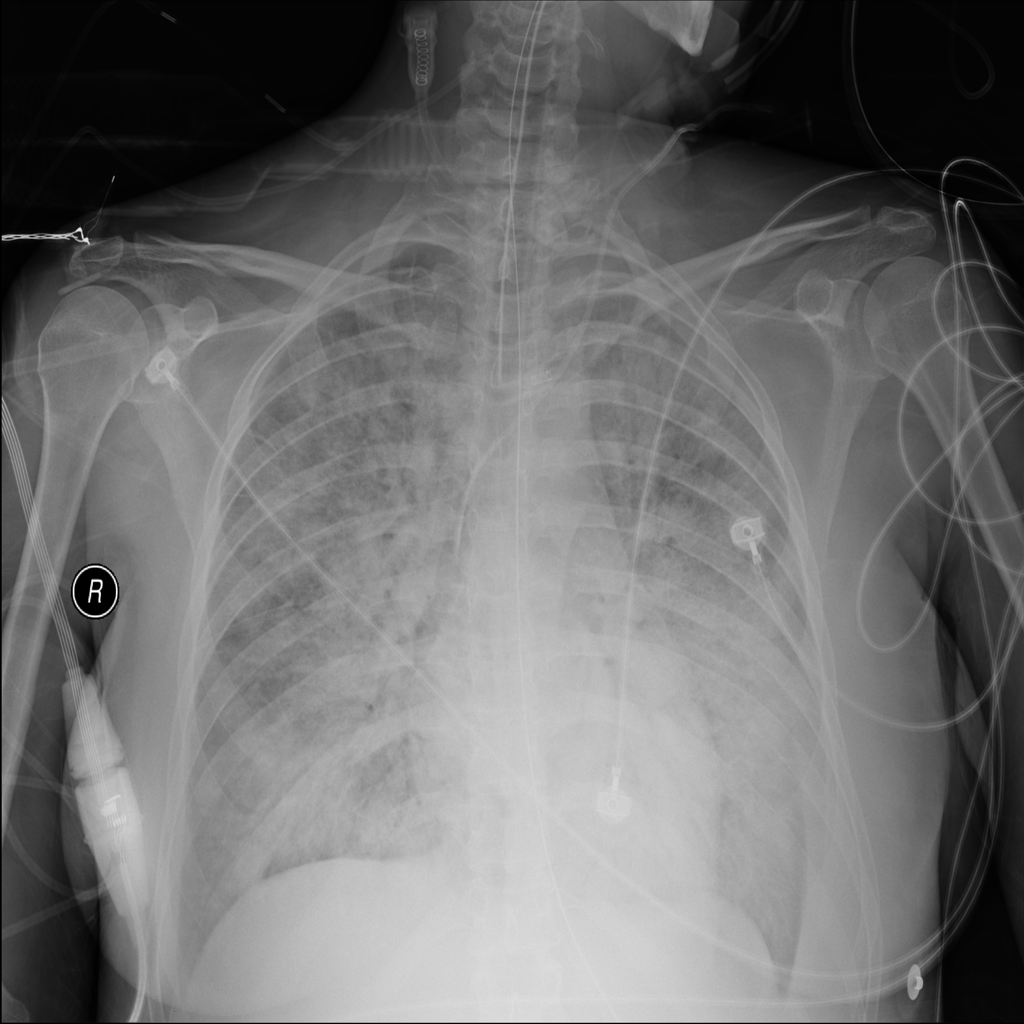

PAT-24D9 · IMG-006Edema

PAT-24D9 · IMG-006

AP